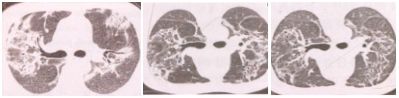

2. 支气管血管束型

支气管血管束及小叶间隔增厚,可伴小囊腔形成。

3. 肺泡间质型

双肺磨玻璃影或条索状阴影,可伴有支气管血管束增粗弥漫网格影,伴支气管扩张症。